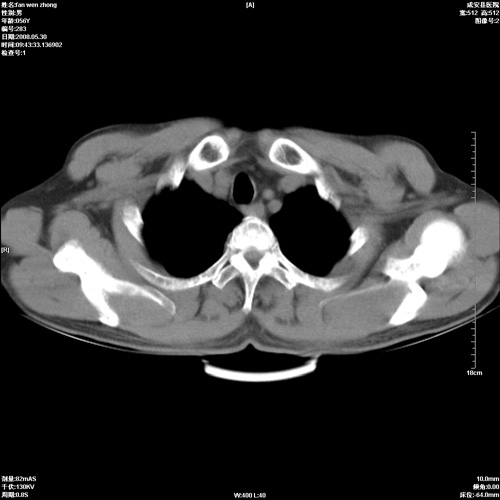

病人 男 56岁 一周前高热,体温达39-40度,经抗炎治疗后,体温渐降,达37,5-38度,轻微咳嗽,胸部不适 查白细胞为1.3万 行ct检查,请分析。

双肺内可见多发结节状病灶,并见小空洞,病人高热,白血球增高,应该是典型的迁徙性肺脓肿(多为金黄色葡萄球菌感染)。查一下口腔等其它部位有无感染灶。

双肺内可见多发结节状病灶,并见小空洞,病人高热,白血球增高,应该是典型的迁徙性肺脓肿(多为金黄色葡萄球菌感染)。建议治疗后复查.